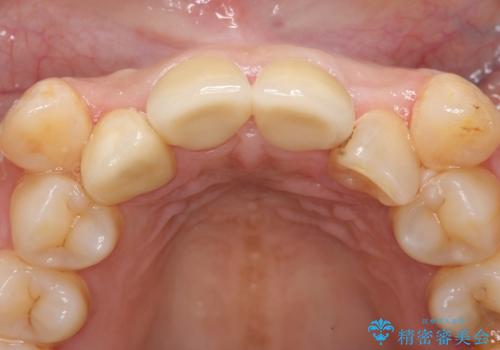

その後右上1,2番目及び左上1番目の歯に対してオールセラミッククラウンによる補綴を行いました。

今回用いたオールセラミッククラウンはジルコニアフレームという白い素材の上にセラミックを盛っているため、審美性が非常に高いのが特徴です。

また、ジルコニアは人工ダイヤモンドの材料にも使われているほど高い強度を持っており、そのためオールセラミッククラウンは審美性だけでなく、奥歯やブリッジの補綴も可能とするクラウンです。